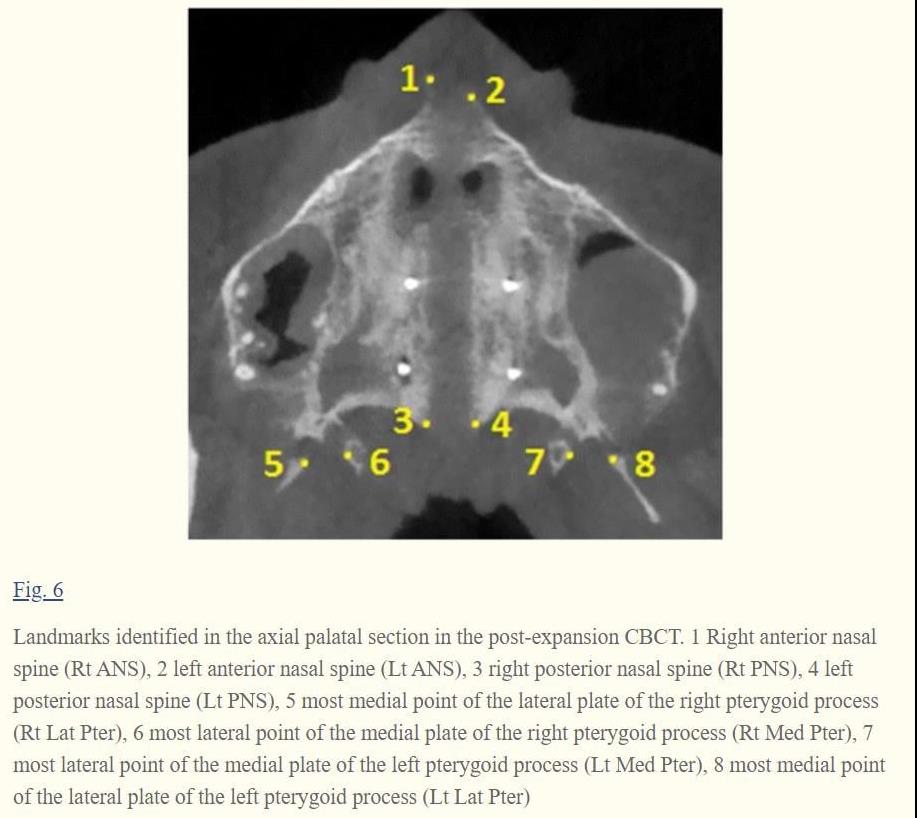

Mini-implant-assisted rapid palatal expansion (MARPE) appliances have been developed with the aim to enhance the orthopedic effect induced by rapid maxillary expansion (RME). Maxillary Skeletal Expander (MSE) is a particular type of MARPE appliance characterized by the presence of four mini-implants positioned in the posterior part of the palate with bi-cortical engagement. The aim of the present study is to evaluate the MSE effects on the midpalatal and pterygopalatine sutures in late adolescents, using high-resolution CBCT. Specific aims are to define the magnitude and sagittal parallelism of midpalatal suture opening, to measure the extent of transverse asymmetry of split, and to illustrate the possibility of splitting the pterygopalatine suture.

Midpalatal suture was successfully split by MSE in late adolescents, and the opening was almost perfectly parallel in a sagittal direction. Regarding the extent of transverse asymmetry of the split, on average one half of ANS moved more than the contralateral one by 1.1 mm. Pterygopalatine suture was split in its lower region by MSE, as the pyramidal process was pulled out from the pterygoid process. Patient gender and age had a negligible influence on suture opening for the age group considered in the study.